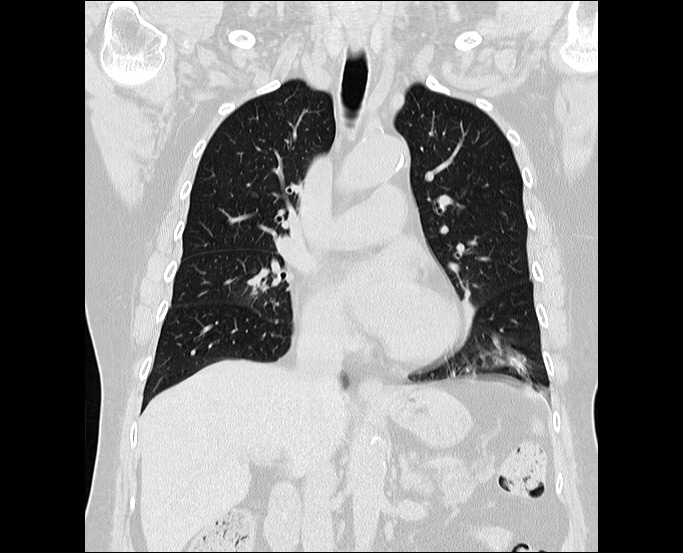

흉부 CT, 저선량흉부 CT, 폐 CT 여러 용어로 설명되는 가슴 부위의 CT에 대하여 최대한 알기 쉽게 설명드리겠습니다.

폐(가슴) 부위의 진행되는 CT 검사의 종류는 크게 두 가지로 나눠지고 방사선피폭량에 따라 구분됩니다.

다양한 질환을 진단하는 데 사용되며 시각화된 영상을 통해 쉽게 병변을 진단할 수 있기 때문에 많은 장점이 있습니다. 어떤 질환 진단을 할 수 있는지 알아보겠습니다.

폐 전반의 모든 질환을 쉽게 관찰할 수 있기 때문에 폐 질환의 진단과 치료에 매우 중요한 역할을 하고 있습니다.